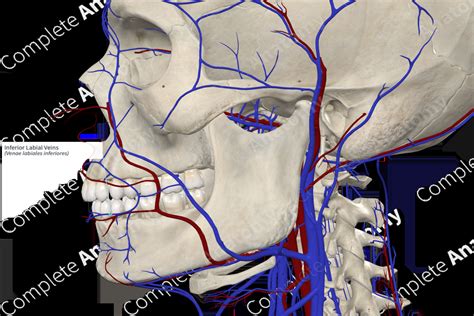

Alright, let’s get down to the nitty-gritty of the inferior labial anatomy. When we look at the lower lip, it’s not just a simple flap of skin. It’s a sophisticated structure made up of several distinct layers, each with its own specific job. Starting from the outside, we have the skin, which is the protective outer layer. Beneath the skin, you’ll find the subcutaneous tissue, a layer of fat and connective tissue that provides some cushioning and allows for movement. Then comes the really interesting part: the muscles. The primary muscle associated with the inferior labial is the orbicularis oris , specifically its lower fibers. This muscle acts like a sphincter, encircling the mouth and enabling us to pucker, whistle, and form various lip shapes for speech. But it’s not just the orbicularis oris; other muscles of facial expression also insert into or act upon the lower lip, influencing its movement. Think about the depressor anguli oris (also known as the ‘tragedy muscle’), which pulls down the corners of the mouth, or the mentalis , which lifts the lower lip and protrudes the chin. So, you can see how interconnected everything is! Below the muscles, we encounter the submucosa, which contains salivary glands – those little guys that keep our lips moist and aid in digestion. These are often referred to as labial salivary glands. Finally, we have the oral mucosa, the inner lining of the lip, which is a moist mucous membrane that directly contacts food and saliva. This intricate layering allows for the incredible range of motion and sensation we experience in our lower lip. The blood supply to the inferior labial is also quite rich, primarily coming from branches of the facial artery, specifically the inferior labial artery. This ensures that the tissues have plenty of oxygen and nutrients. And for sensation, various branches of the trigeminal nerve, particularly the mental nerve (a branch of the inferior alveolar nerve), provide feeling to the lower lip. This rich innervation is why even a slight touch on your lower lip can be so noticeable!